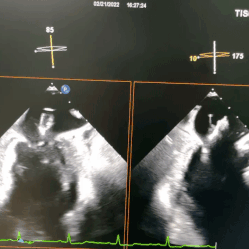

术中超声

基于前期多学科团队的精准评估、术中专业团队精湛高深的手术技巧以及精良的TruDelta®经导管二尖瓣瓣膜系统,本次手术圆满成功,术后即刻超声显示二尖瓣反流消失,瓣膜植入位置理想,支架贴合牢固,无瓣周漏,二尖瓣前向血流通畅,结果令人满意。